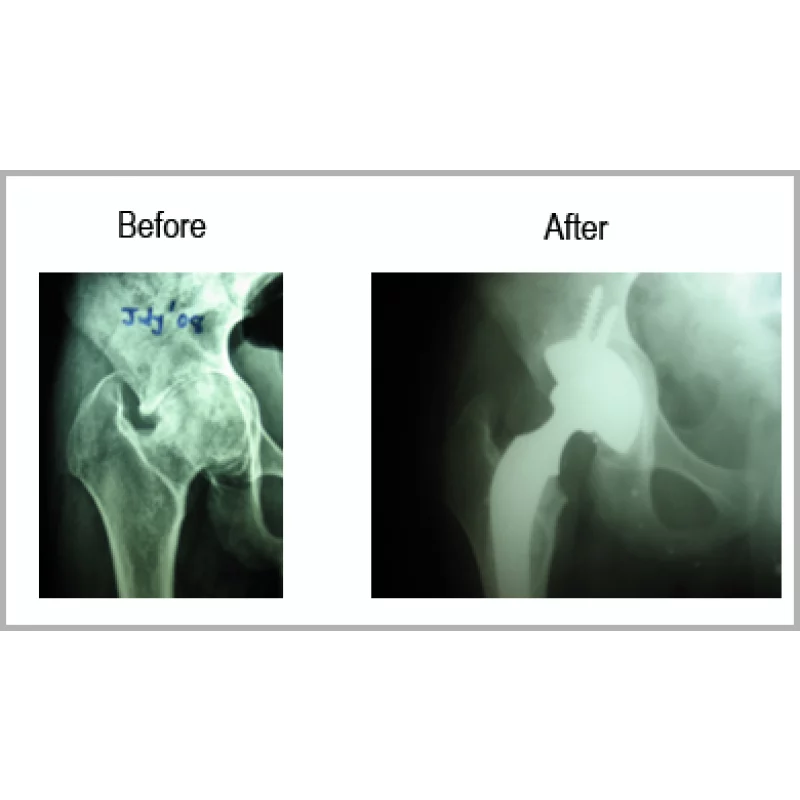

A Young Boy Aged 22 Years Had Fall From Height Before Few Years. He Had Injury Over Right Hip. He Did Not Have Proper Treatment. He Had Extreme Pain So Much So That He Could Not Keep His Right Foot On The Ground. He Had Shortening Of 2.5 Centimetres. He Had Protrusio Acetabulum.He Had Right Total Hip Replacement With Bone Grafting For Acetabulum. His Shortening Is Totally Corrected And Walking Normally.... Read more